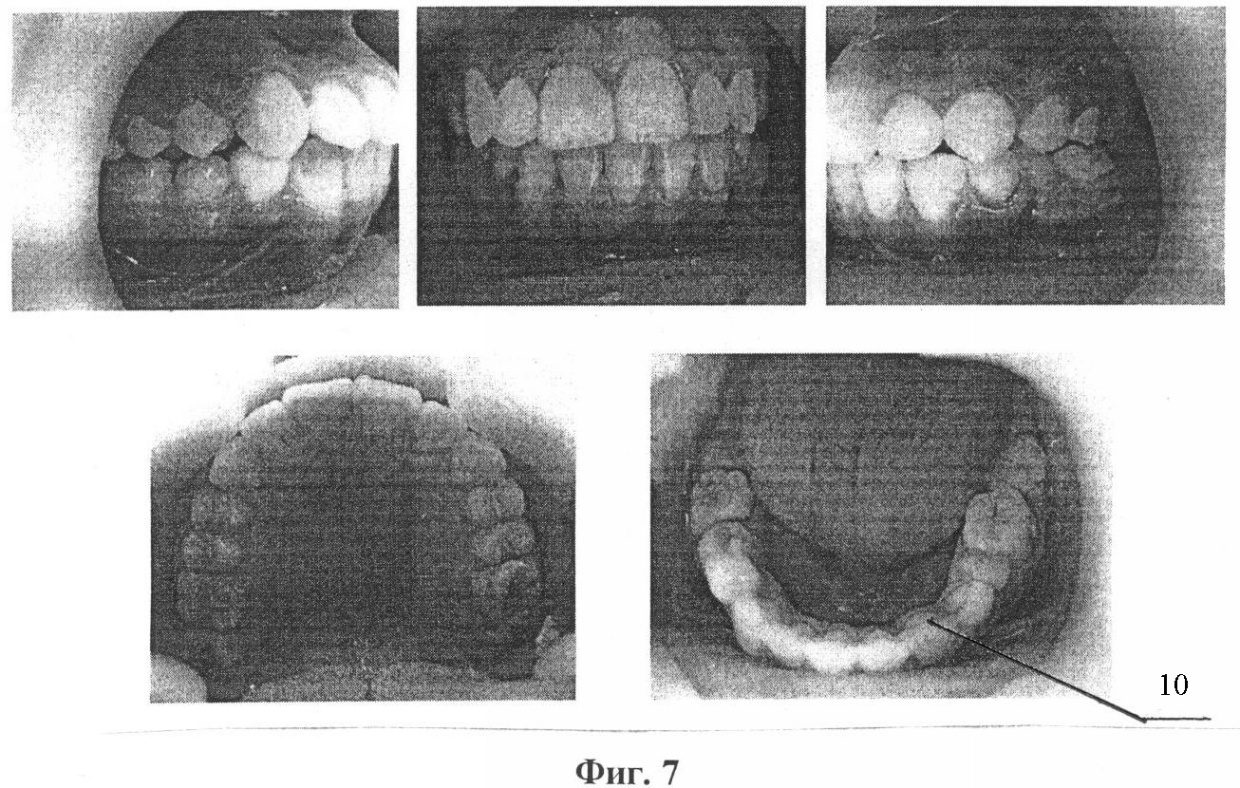

Изобретение иллюстрируется фотографиями, где на фиг.1 и 2 показаны зубные ряды верхней и нижней челюстей пациентки А., на фиг.3 – расположение несъемного аппарата с тремя направляющими на верхней челюсти для расширения и удлинения верхнего зубного ряда (стрелками указано направление активации винта), на фиг.4 показана реплантация клыка и премоляра, фиксация брекетов на эти зубы, шинирование в зубном ряду при помощи ортодонтической дуги и металлических лигатур, разобщение прикуса за счет окклюзионных накладок из стеклоиономерного цемента на 36 и 46 зубы, на фиг.5 показаны фотографии зубных рядов пациентки А. после ортодонтического лечения, на фиг.6 показана фиксация брекетов, колец и небного бюгеля на зубы верхней челюсти, на фиг.7 – зубные ряды пациентки А. верхней и нижней челюстей после ортодонтического лечения, на фиг.8 – ортопантомограмма пациентки А. до ортодонтического лечения, на фиг.9 – ортопантомограмма пациентки А. через 6 месяцев после реплантации клыка и премоляра, на фиг.10 – ортопантомограмма пациентки А. после ортодонтического лечения, на фиг.11 – телерентгенограммы пациентки А. до и после ортодонтического лечения, на фиг.12 и 13 – гипсовые модели пациентки А. до и после ортодонтического лечения соответственно.

Клинический пример. Пациентка А., 12 лет 6 мес., (история болезни 9100018802) обратилась в детскую поликлинику с жалобами на некрасивую улыбку, выступание вперед верхних клыков, наличие двух клыков на нижней челюсти справа, один из которых развернут на 180°, отсутствие клыка на нижней челюсти слева (фиг.1).

После окончания активного ортодонтического лечения профиль и улыбка пациентки А. (14 лет 6 мес.) значительно улучшились (фиг.7). На верхнюю челюсть был изготовлен съемный ретейнер и несъемный на зубы нижней челюсти (фиг.8). Реплантированные зубы болезненных ощущений у пациентки А. не вызывали на протяжении всего курса ортодонтического лечения. При осмотре полости рта подвижности этих зубов не наблюдалось. Электроодонтодиагностика клыка после снятия брекетов была равна 13 мкА, премоляра – 19 мкА.

Нестандартность проведенного комплексного лечения состояла в применении брекет-системы и несъемного аппарата с тремя направляющими (винт Бертони) для расширения и удлинения верхнего зубного ряда и реплантации клыка и премоляра с использованием синтетического коллаген-апатитового материала «ЛитАр» для оптимизации репаративного остеогенеза. У данной пациентки проведена компьютерная томография верхней и нижней челюсти, ортопантомография и телерентгенография, изучение гипсовых моделей челюстей до и после ортодонтического лечения (фиг. 9, 10, 11, 12, 13, 14).

Следует учитывать, что после реплантации клыка и премоляра анкилоз корневой части зуба не возник, что могло бы привести к нарушению функций опорного аппарата зуба, что в будущем привело бы к несостоятельности использовать их в качестве опоры при протезировании. Реплантированные клык и премоляр находятся в зубном ряду неподвижно, активно участвуют в акте жевания, по цвету не отличаются от соседних зубов. Косметически и функционально результат ортодонтического лечения полностью удовлетворяет пациентку и ее родителей.